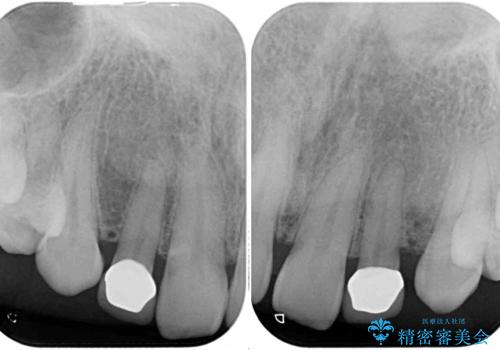

- 前歯の矮小歯に貼り付けられていたラミネートベニアが外れてしまったとのことで来院された患者様です。

反対側の矮小歯は裏打ちが金属であったため、両方の歯ともにオールセラミッククラウンにて補綴することとしました。